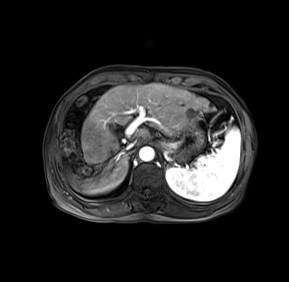

05-16,MRI: 肝脏多发异常信号影 肝硬化,脾大;右侧胸腔积液。

术后一月余,肝内广泛转移